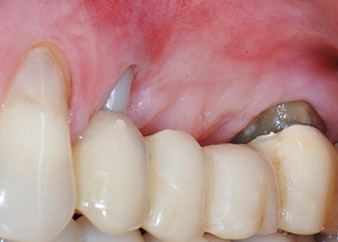

Фигури 17 и 18 показват клиничния резултат два месеца след операцията. Зъб 24 показва намалена подвижност на Милър клас 1 и меките тъкани не са възпалени. Сондирането е избегнато на този етап, за да се избегне повторно възпаление и нарушение на епителната надстройка. Планиран е контролен преглед за повторно отваряне и поставяне на оздравителни абатмънти, шест месеца след поставяне на имплантите.